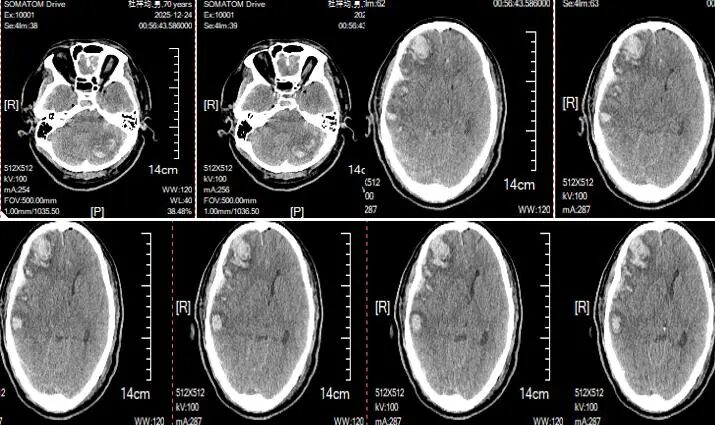

术后两周复查头颅CT显示,血肿完全清除

术后两周复查胸部CT显示,肺部情况好转